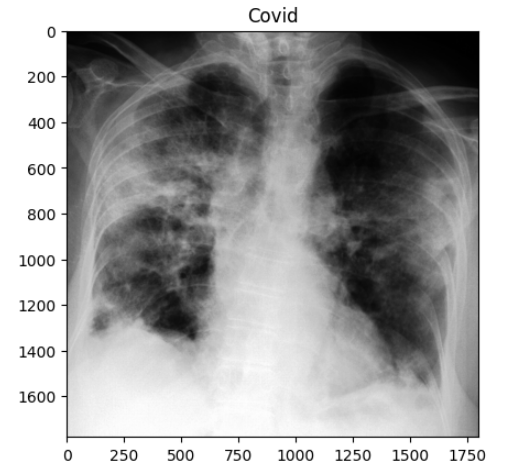

◼ 이미지를 읽어와 RGB 형식으로 변환하고, 'Normal', 'Covid', 'Viral Pneumonia' 이미지를 표시

@interact(index=(0, min_num_files-1))

def show_samples(index=0):

# 선택된 인덱스에 해당하는 이미지를 각 클래스에서 읽어옴

normal_image = get_RGB_image(data_dir, normals_list[index])

covid_image = get_RGB_image(data_dir, covids_list[index])

pneumonia_image = get_RGB_image(data_dir, pneumonias_list[index])

plt.figure(figsize=(12, 8))

plt.subplot(131)

plt.title('Normal')

plt.imshow(normal_image)

plt.subplot(132)

plt.title('Covid')

plt.imshow(covid_image)

plt.subplot(133)

plt.title('Pneumonia')

plt.imshow(pneumonia_image)

plt.tight_layout() # 서브플롯 간의 간격을 자동으로 조정하여 레이아웃 정리